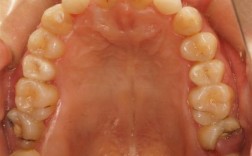

(图片来源网络,侵删) - 取模/扫描: